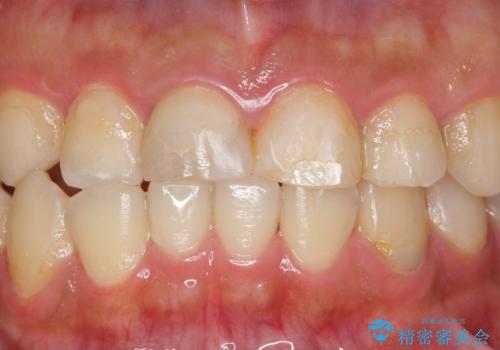

咬み合わせが悪く矯正も検討されていたそうですが、歯を真っ白にしたいというご希望もあり、28本のすべての歯をセラミックにしたいとのことでした。

精査したところ、ほとんどの歯が保険内のレジンで充填されており、咬み合わせも悪く咬合していない歯もありました。

虫歯をしっかりと治療したのち、オールセラミッククラウンによる補綴治療を行いました。